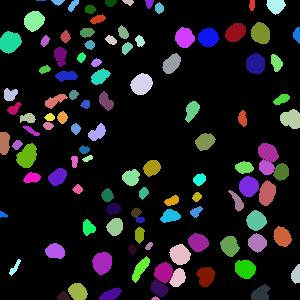

4.1.1 Voronoi labels

A Voronoi diagram is a partitioning of a plane into convex polygons (Voronoi cells) according to the distance to a set of points in the plane. There is exactly one point (seed point) in each cell and all points in a cell are closer to its seed point than other seed points. In our task, the detected points in an image can be treated as seed points to calculate the Voronoi diagram as shown in Fig. 1(b). For each Voronoi cell, assuming that the corresponding nucleus is located within the cell, then the Voronoi edges separate all nuclei well and the edge pixels belong to the background. This assumption holds for most of the nuclei because the detected points are around the centers and nuclear shapes are nearly convex (Fig. 3(b)).

Assigning the Voronoi edges as background pixels and the detected points (dilated with a disk kernel of radius 2) as nuclei pixels, we obtain the Voronoi point-edge label (Fig. 3). All other pixels are ignored during training. Note that although the pixels on the Voronoi edge between two touching nuclei may not necessarily be background, the edges are still helpful in guiding the network to separate the nuclei. The Voronoi labels aim to segment the central parts of nuclei and are not able to extract the full masks, because they lack the information of nuclear boundaries and shapes. To overcome this weakness, we generate another kind of labels that contain this complementary information.

The cluster label (Fig. 1(b)) is generated by refining the clustering result with morphological dilation and erosion, which are done separately in each Voronoi cell to avoid connecting close nuclei. The cluster labels have more shape information about the nuclei compared with the Voronoi labels, at the expense of more errors and uncertainties. We argue that these two types of labels are complementary to each other and will jointly lead to better results.